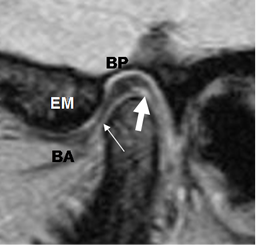

Fig 6B. Disco normal.

RM GE sagital oblicuo, con boca abierta. BA: Banda anterior. BP: Banda posterior. Zona intermedia: Flecha delgada. EM: Eminencia media.